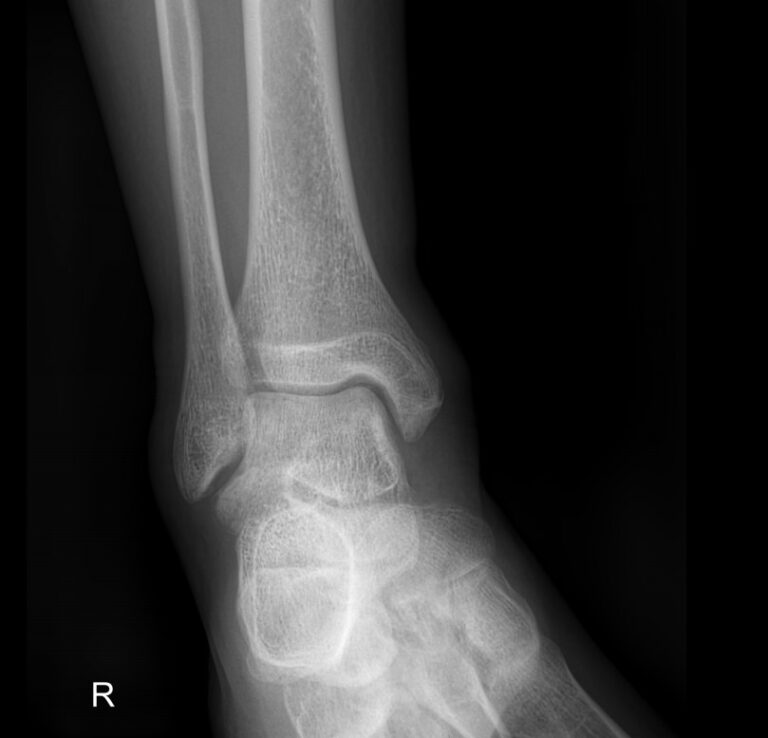

Голеностопные суставы отличаются сложным строением, в позволяющим стопе вращаться, сгибаться и разгибаться почти на 90о. Благодаря этому тело свободно перемещается в пространстве, меняет свое положение, поднимает собственный вес и дополнительный груз. Травмы голеностопных суставов встречаются также часто, как и хронические заболевания.

В качестве скринингового, а зачастую и единственного метода диагностики голеностопных суставов обычно используют рентген. Его вполне достаточно для визуализации внутреннего строения сустава и патологических изменений в нем. А цифровая нагрузка цифрового оборудования последнего поколения  несет минимум излучения и позволяет безопасно делать несколько снимков подряд.

Что покажет рентген голеностопных суставов

• Изменения, произошедшие в костной ткани элементов суставов ― разрежение, некроз, озлокачествление, склерозирование;

• Нарушение четкости контуров костных образований;

• Перелом, его местоположение, смещение отломков;

• Состояние суставных щелей ― сужение, расширение, скопление жидкости, обызвествление капсулы;

• Конгруэнтность суставных поверхностей или вывих;

• Состояние мягких тканей ― отеки, инородные тела.